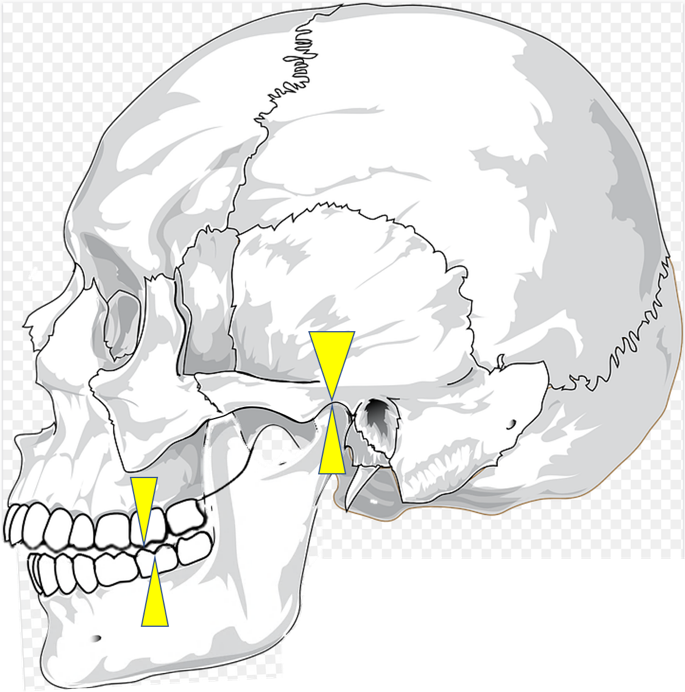

中心位

これは、左右の顎の関節にも余計な負荷がかからずに、そして顎を閉じる筋肉もリラックスした状態で、正しいかみ合わせの高さで、咬んだときのかみ合わせのことです。

先ほど説明した、このかみ合わせの位置を中心位、といいます。

そこで出てくるのが、中心位です。中心位は、歯がなくても決まります。顎や筋肉がリラックスした状態で、顎をそっと閉じてくれば良いからです。

そのような場合も、上下の歯はあるけど、中心位でかみ合わせを再構成することがあります。